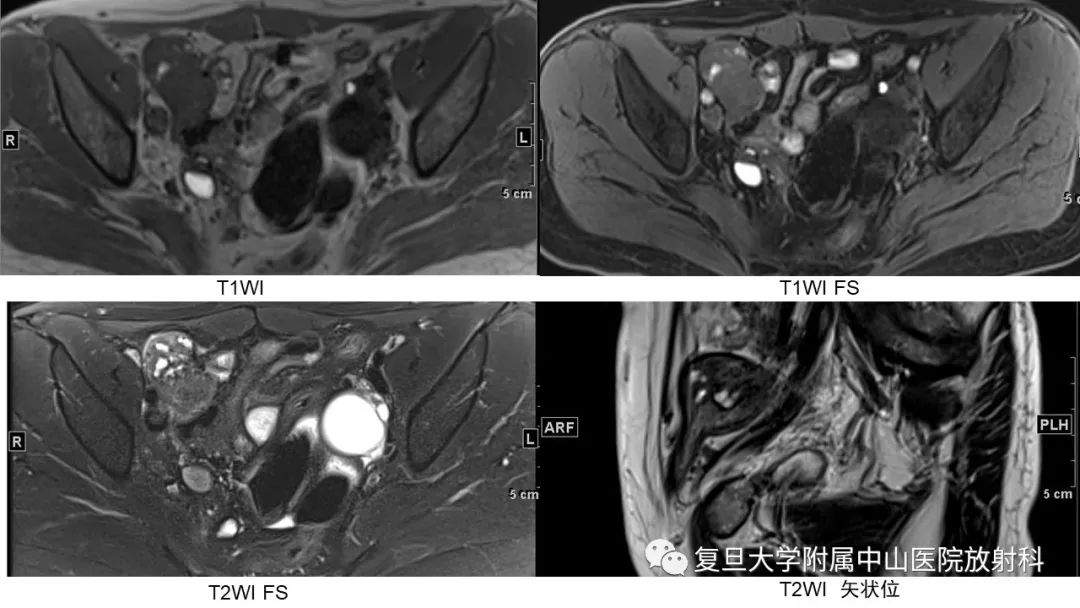

【病例】子宫腺肌瘤1例MR影像

【病例】子宫腺肌瘤1例MR影像-1